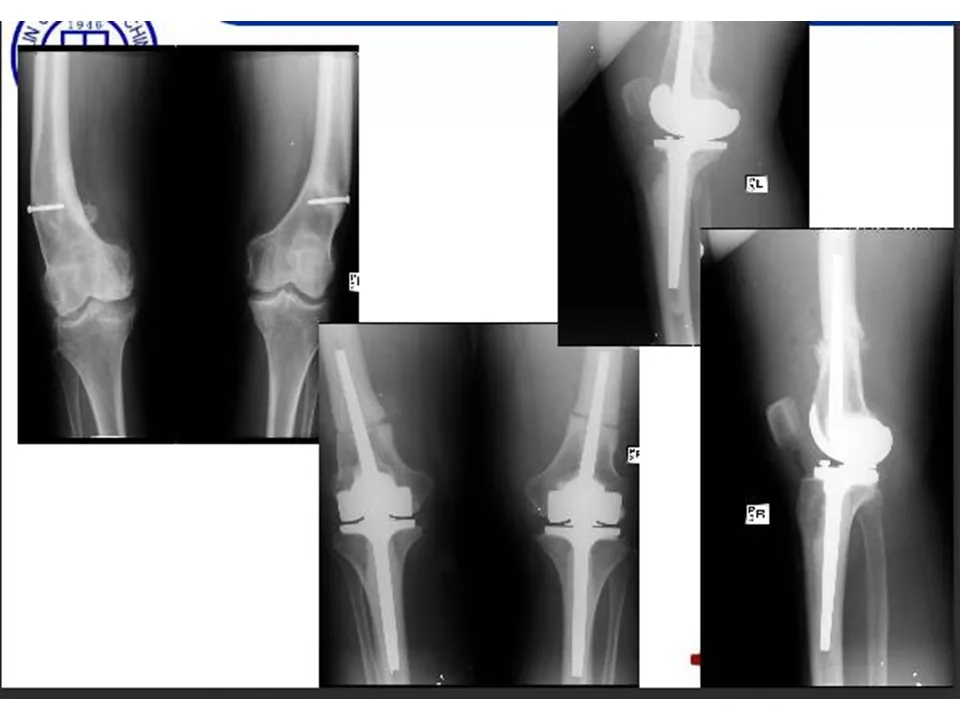

>【骨科PPT】全膝关节置换的截骨原则

【骨科PPT】全膝关节置换的截骨原则